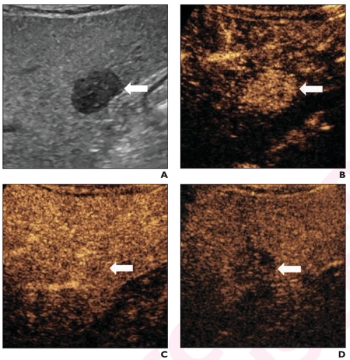

In addition to over 90 percent sensitivity in detecting hepatocellular carcinoma (HCC), the glypican-3 (GPC3) targeted PET tracer 68Ga-aGPC3-scFv appeared to be advantageous in identifying HCC tumors smaller than one centimeter, according to pilot study findings presented at the SNMMI conference.

In a new literature review, researchers discussed key considerations with the use of B-mode ultrasound and contrast-enhanced ultrasound in the detection of hepatocellular carcinoma.